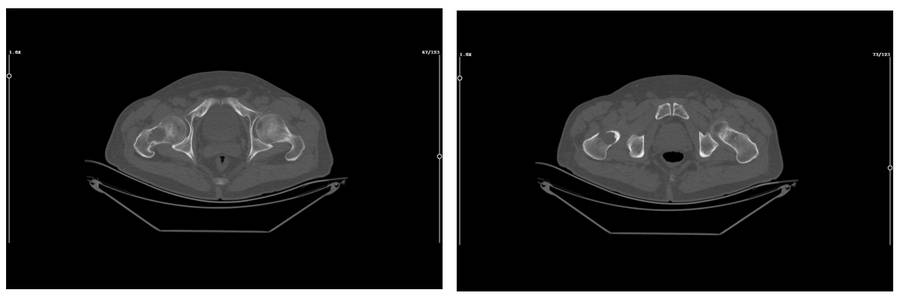

Before the surgery: The CT scan also shows destruction in the anterior cortex.